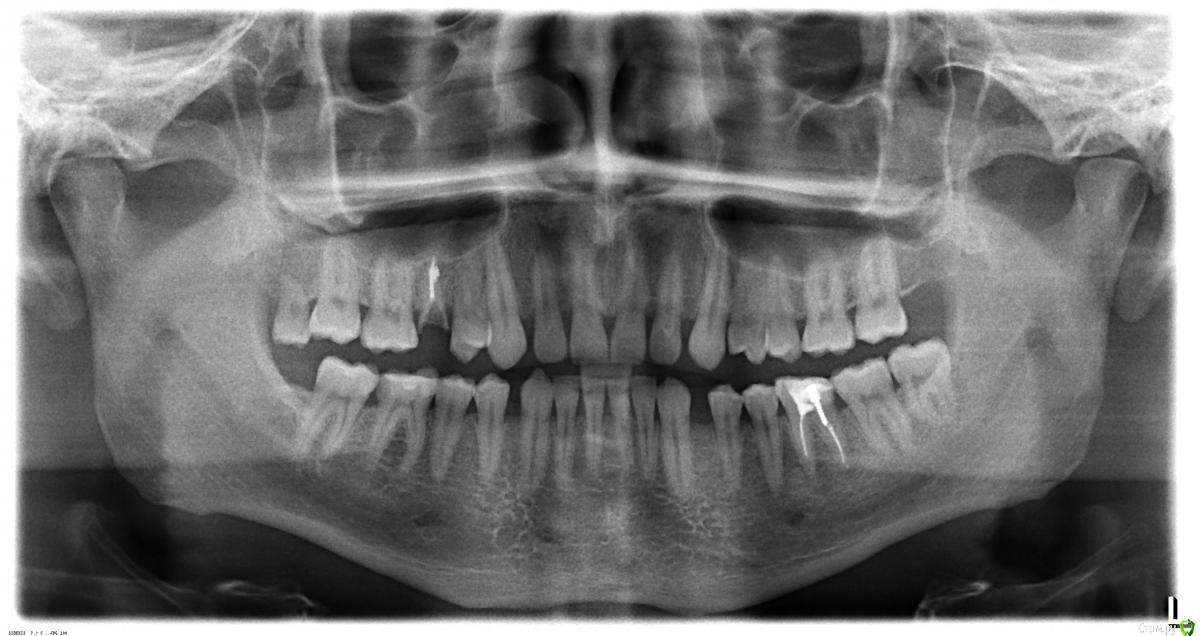

akudja Опубликовано 11 января, 2017 Поделиться Опубликовано 11 января, 2017 (изменено) Доброго времени суток.Интересует другое мнение по ситуации с зубами, есть три ортопантомограммы сделанные в разный промежуток времени:04.04.2014 14.06.2016 11.01.2017 1. Кто либо видит где нибудь кисту по этим снимкам?2. Действительно ли каналы 36го зуба (правый нижний ряд по снимку, 6ой зуб) недопломбирован/ы?3. Наиболее оптимальное решение для указанного в вопросе № 2 зуба - доделка и установка коронки или удаление с последующей имплантацией?4. 18й зуб (левый верхний ряд, последний зуб) есть ли необходимость в его удалении при условии, что он здоров, соседние зубы не трогает и им не мешает, владельцу зуба также никаких неудобств не доставляет? Так как будучи пациентом удостовериться в достоверности диагноза врача нет возможности, остается уповать на его добросовестность, но хотелось бы иметь разностороннюю точку зрения. Заранее благодарю за ответы. Изменено 11 января, 2017 пользователем akudja Ссылка на комментарий

red_butler Опубликовано 12 января, 2017 Поделиться Опубликовано 12 января, 2017 1. Кто либо видит где нибудь кисту по этим снимкам? для постановки данного диагноза требуется гистологическое исследование. 2. Действительно ли каналы 36го зуба (правый нижний ряд по снимку, 6ой зуб) недопломбирован/ы? да 3. Наиболее оптимальное решение для указанного в вопросе № 2 зуба - доделка и установка коронки или удаление с последующей имплантацией? Для ответа нужен очный осмотр 4. 18й зуб (левый верхний ряд, последний зуб) есть ли необходимость в его удалении при условии, что он здоров, соседние зубы не трогает и им не мешает, владельцу зуба также никаких неудобств не доставляет? удаляйте, зуб лишен антагониста, выдвинулся и поражен кариесом. 1 Ссылка на комментарий